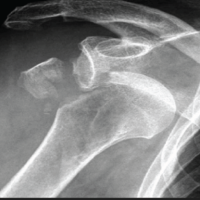

Bilateral TMJ ultrasound was carried out with an ultrasound system, Philips EPIQ 5 (Bothell, Washington, USA), high-frequency linear array transducer (12.5 MHz) that is optimized with regard to superficial musculoskeletal structures. Patients were positioned in the supine position with slight neck extension, and a standard set of scanning protocols was used. The transducer was placed in sagittal and coronal views on the region of the TMJ, and evaluations were done in closed-mouth and open-mouth positions to determine dynamic disc displacement (Fig. 2).

Figure 2: Musculoskeletal ultrasound for the temporomandibular joint.

Systematic evaluations in MSKUS

(1) Joint effusion, determined by the presence of an anechoic or hypoechoic fluid collection in the joint space with a maximum dimension of more than 2 mm (2) Synovitis, identified by a hypoechoic synovial hypertrophy with augmented vascularity as observed on power Doppler imaging (Doppler settings: pulse repetition frequency 750 Hz, Doppler gain set slightly lower than noise level), (3) disc displacement, determined by identifying the articular disc as a hypoechoic biconcave structure positioned anterior to the condylar head in the closed-mouth view and failing to resume its normal interposed position during mouth opening.